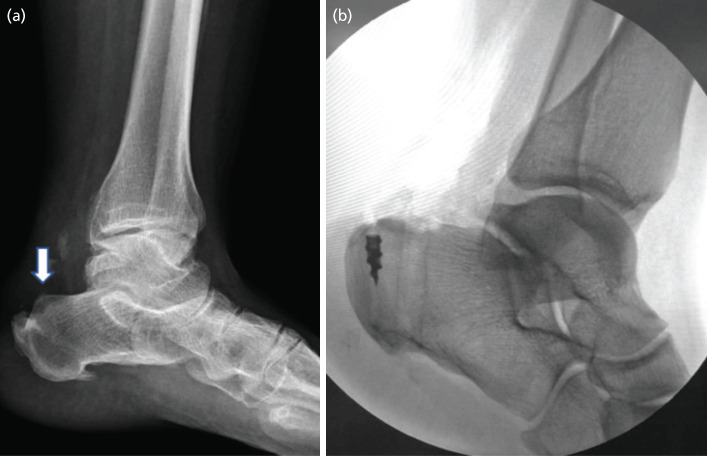

Abstract Image